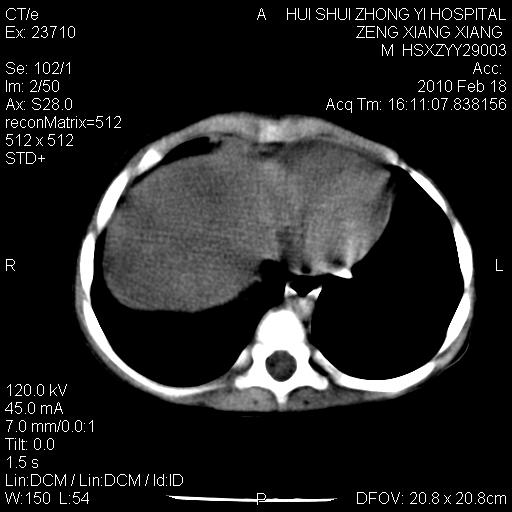

标题: PED3106:男,2岁,腹胀1月。 [打印本页]

标题: PED3106:男,2岁,腹胀1月。

定位腹膜后,肾上腺来源;

定性:恶性神经源性,肾上腺神经节母细胞瘤可能性大。

鉴别:肝母、肾母、肝脏中胚层错构瘤。

依据:年龄、有钙化,肾脏及肝脏受压移位。

肝母细胞瘤可能性大,右肾形态大体可见,不支持肾母细胞瘤,右肾移位不明显,肾上腺神经母细胞瘤可能性不大。